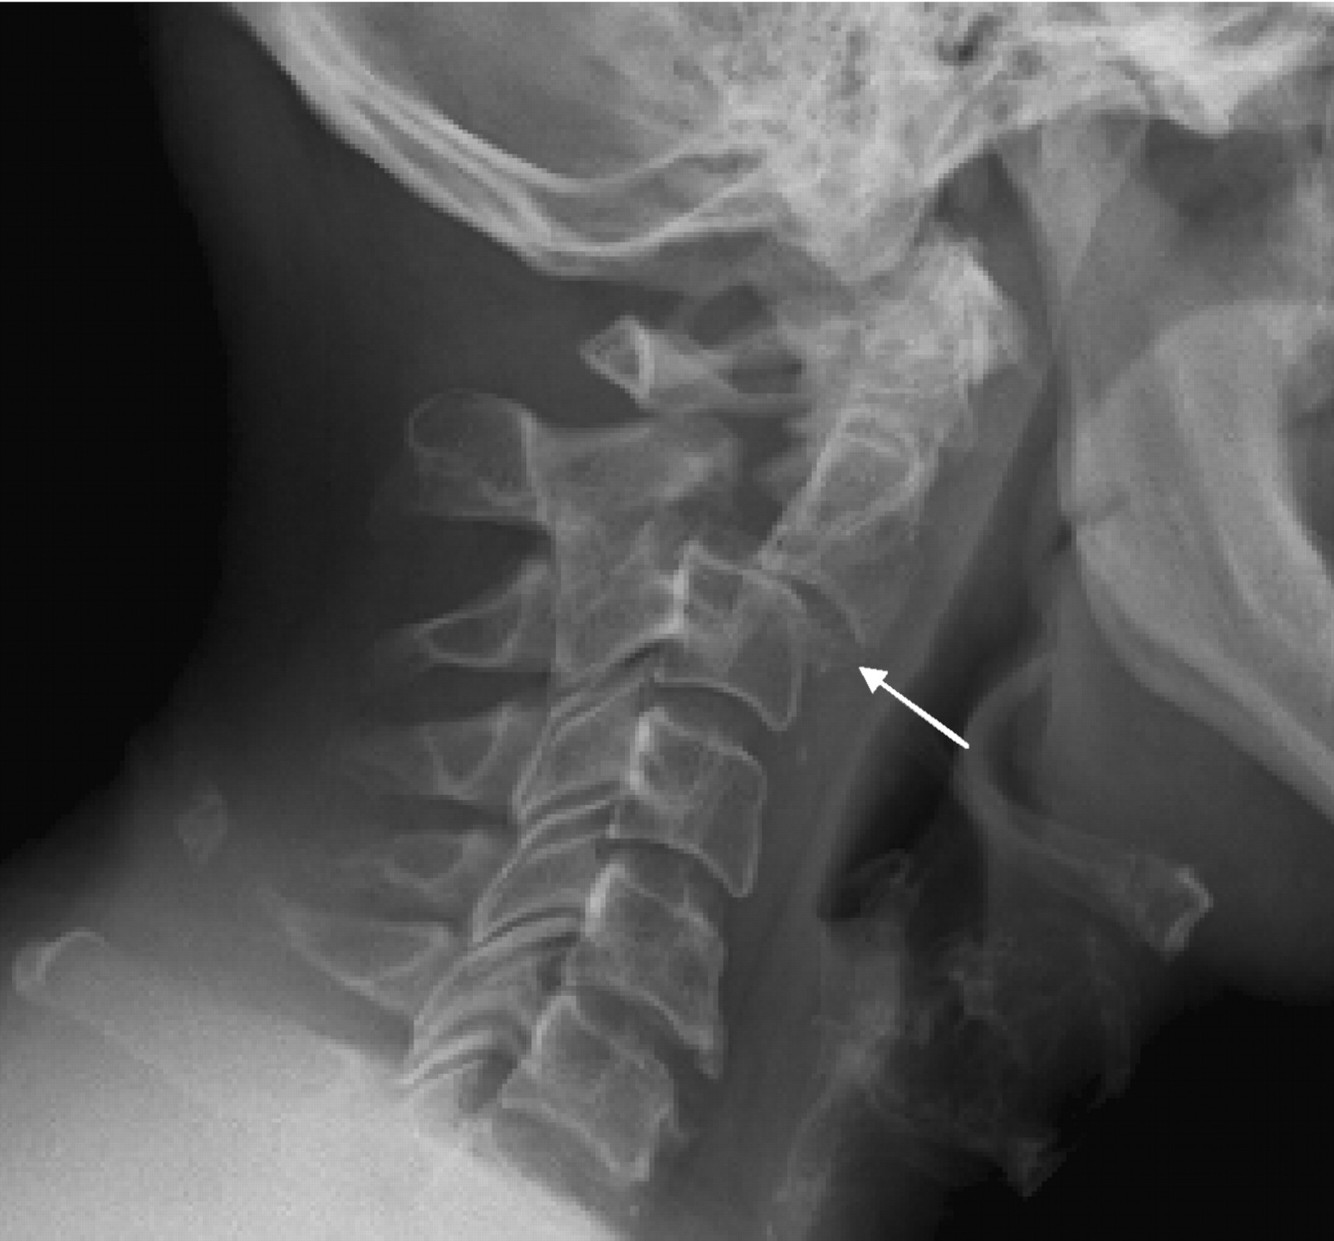

hangmans fracture

Jeffersons fracture